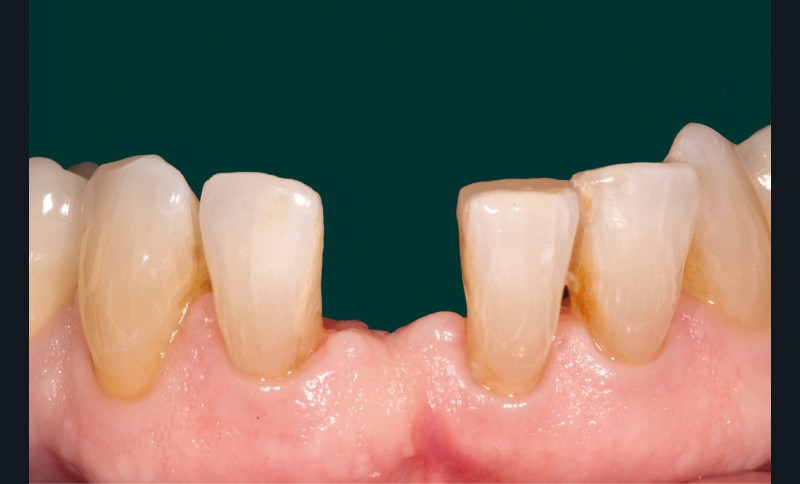

La patiente est venue consulter à la suite du descellement de la pièce zircone qui, agissant comme une attelle de contention, subissait des contraintes de torsion importantes. Malgré plusieurs tentatives infructueuses de remise en place (fig. 3), nous avons proposé à la patiente, compte tenu des rapports occlusaux favorables, de réaliser un bridge cantilever en disilicate de lithium (IPS e.max, Ivoclar Vivadent) plus apte au collage [1]. Cette thérapeutique est un choix biologique et biomécanique séduisant, validé par la littérature scientifiquement [2].

À l‘époque de la réalisation de l’attelle, le choix du matériau se faisait entre le métal et la zircone. Les inconvénients majeurs de ces deux matériaux résident dans la complexité du protocole de collage [3] d’une part, et dans le manque de fiabilité à long terme de ce dernier, d’autre part (fig. 4).

S’ajoutent à cela des difficultés de repositionnement en cas d’échec du collage initial.